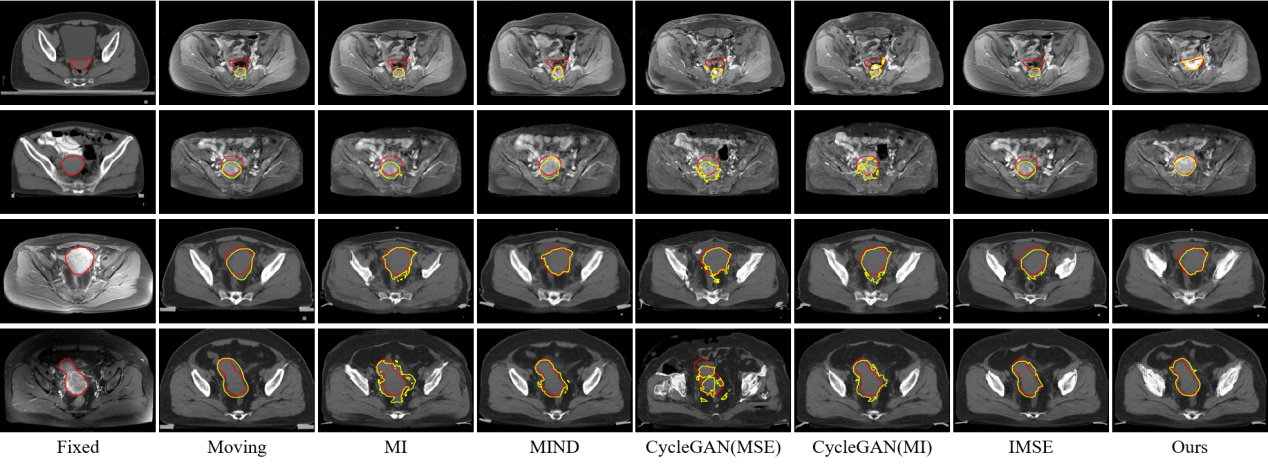

研究结果表明,SynMSE 在L2R 2022 CT-MR腹部数据集、临床宫颈CT-MR数据集以及CuRIOUS MR-US脑数据集上均取得了最优配准性能。与传统方法相比,SynMSE显著提升了Dice系数、降低了HD95与TRE误差,实现了在复杂模态差异下的高精度解剖结构对齐。图4-图6分别为所提出方法在三个数据集上的定性结果展示,红色标注代表固定图像的目标器官区域,黄色标注代表浮动图像与配准后图像的目标器官区域。表示图中结果显示,SynMSE更好的克服了多模态图像间的复杂分布差异,不仅实现了更精确的配准效果,而且有效保持了组织边界与解剖拓扑的完整性,明显优于现有方法。

图4:所提出方法与现有方法在L2R 2022 CT-MR腹部数据集上的定性效果

图5:所提出方法与现有方法在临床宫颈CT-MR数据集上的定性效果